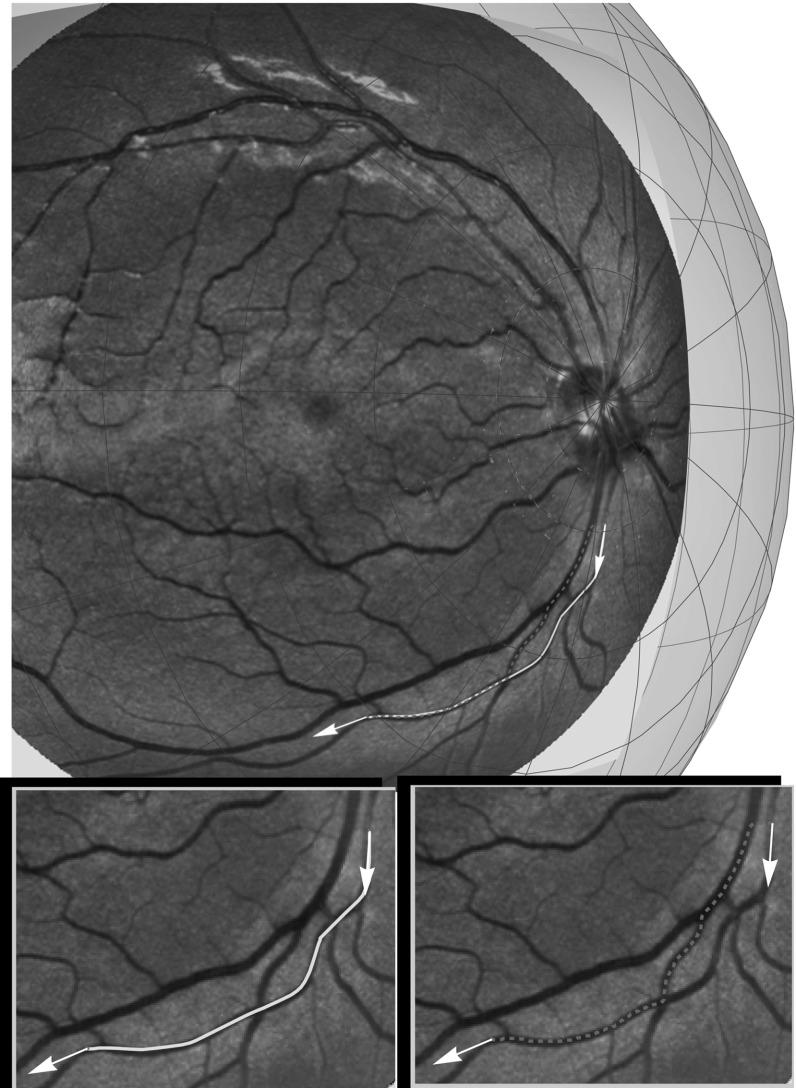

In order to detect salient lines in spherical images, we consider the problem of minimizing the functional for a curve on a sphere with fixed boundary points and directions. The total length is free, denotes the spherical arclength, and denotes the geodesic curvature of  . Here the smooth external cost is obtained from spherical data. We lift this problem to the sub-Riemannian (SR) problem in Lie group and show that the spherical projection of certain SR geodesics provides a solution to our curve optimization problem. In fact, this holds only for the geodesics whose spherical projection does not exhibit a cusp. The problem is a spherical extension of a well-known contour perception model, where we extend the model by Boscain and Rossi to the general case . For , we derive SR geodesics and evaluate the first cusp time. We show that these curves have a simpler expression when they are parameterized by spherical arclength rather than by sub-Riemannian arclength. For case (data-driven SR geodesics), we solve via a SR Fast Marching method. Finally, we show an experiment of vessel tracking in a spherical image of the retina and study the effect of including the spherical geometry in analysis of vessels curvature.

为了检测球面图像中的显著线条,我们考虑在具有固定边界点和方向的球面上,使曲线的泛函最小化的问题。总长度(L)是自由的,(s)表示球面弧长,(\kappa_g)表示(\gamma)的测地曲率。这里,光滑的外部代价(C)是从球面数据中获得的。我们将这个问题提升到李群中的次黎曼(SR)问题,并表明某些SR测地线的球面投影为我们的曲线优化问题提供了解决方案。实际上,这仅适用于其球面投影不出现尖点的测地线。该问题是一个著名的轮廓感知模型的球面扩展,我们将Boscain和Rossi的模型扩展到一般情况。对于(n = 2),我们推导SR测地线并评估第一个尖点时间。我们表明,当这些曲线由球面弧长而不是次黎曼弧长参数化时,它们具有更简单的表达式。对于(n = 3)(数据驱动的SR测地线)的情况,我们通过SR快速行进方法求解。最后,我们展示了在视网膜的球面图像中进行血管跟踪的实验,并研究了在血管曲率分析中纳入球面几何的效果。